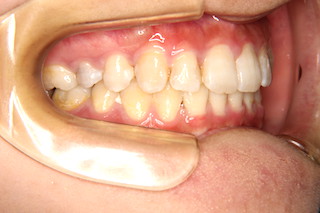

側面・・この角度でも,下の前歯は見えません

側面・・上下とも歯茎のラインもそろってきました!

側面・・奥歯の噛み合わせも綺麗になりました!